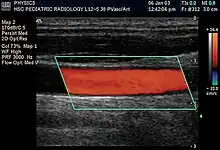

Doppler ultrasonography

Doppler ultrasonography employs the Doppler effect to assess whether structures (usually blood)[56][59] are moving towards or away from the probe, and their relative velocity. By calculating the frequency shift of a particular sample volume, flow in an artery or a jet of blood flow over a heart valve, its speed and direction can be determined and visualized, as an example. Color Doppler is the measurement of velocity by color scale. Color Doppler images are generally combined with gray scale (B-mode) images to display duplex ultrasonography images.[60] Uses include: